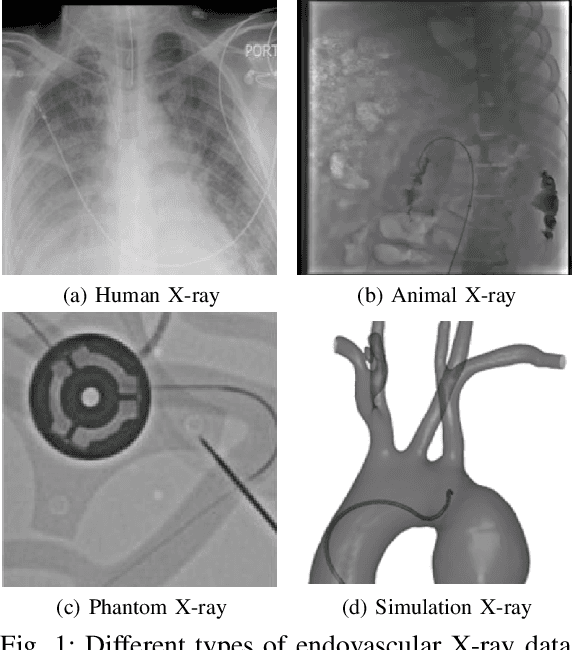

Abstract:In endovascular surgery, the precise identification of catheters and guidewires in X-ray images is essential for reducing intervention risks. However, accurately segmenting catheter and guidewire structures is challenging due to the limited availability of labeled data. Foundation models offer a promising solution by enabling the collection of similar domain data to train models whose weights can be fine-tuned for downstream tasks. Nonetheless, large-scale data collection for training is constrained by the necessity of maintaining patient privacy. This paper proposes a new method to train a foundation model in a decentralized federated learning setting for endovascular intervention. To ensure the feasibility of the training, we tackle the unseen data issue using differentiable Earth Mover's Distance within a knowledge distillation framework. Once trained, our foundation model's weights provide valuable initialization for downstream tasks, thereby enhancing task-specific performance. Intensive experiments show that our approach achieves new state-of-the-art results, contributing to advancements in endovascular intervention and robotic-assisted endovascular surgery, while addressing the critical issue of data sharing in the medical domain.